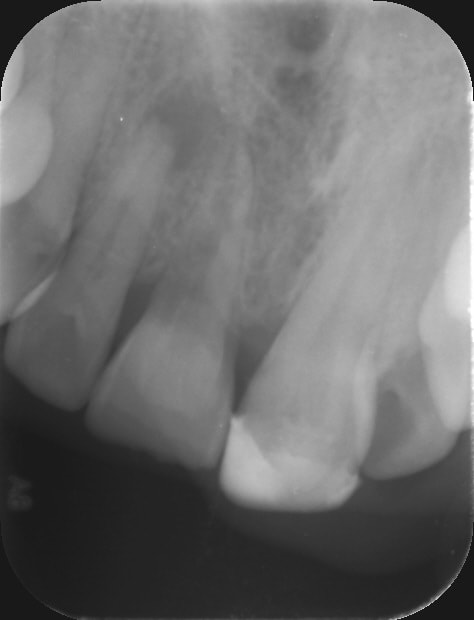

-> y a qu'à voir la radio que je mets dans mon post ... nécrose sans aucune carie sur la dent. On peut avoir des nécroses sur des incisives comme sur des molaires sans aucune carie. Peut être faut il laisser ça en l'état puisque paraît il la meilleure obturation c'est la pulpe.😊

Qu'est-il arrivé à la 21?

vulpi écrivait:

> Qu'est-il arrivé à la 21?

21 bord libre cassé

+ perte osseuse localisée caractéristique d'un trauma occlusale répété.

La 12 doit être un peu mobile, non?

Il n'y a pas de dents manquantes au niveau des secteurs postérieurs?

> -> y a qu'à voir la radio que je mets dans mon post ... nécrose sans aucune

> carie sur la dent. On peut avoir des nécroses sur des incisives comme sur des

> molaires sans aucune carie. Peut être faut il laisser ça en l'état puisque

> paraît il la meilleure obturation c'est la pulpe.😊

Dans ton cas : bord libre fracturé sur 21, résorption sur 11 et nécrose sur 12 et tu veux nous faire croire qu'il n'y a pas eu de trauma?

Une nécrose n'est pas spontanée, il y'a des éléments déclencheurs, mais il est parfois difficile de les mettre en évidence. Des fissures amelaires peuvent conduire à une percolation bactérienne et aboutir à la nécrose. Sur les incisives par exemple tu peux avoir un cingulum très marqué et provoqué une infiltration. Des microtraumatismes répétés, etc, etc...

PS : pour moi ce n'est pas la 12 le principal souci sur ta radio mais bien la 11

oui pour la 11 on a l'impression qu'il y a une résorption. Je vais refaire une radio plus nette